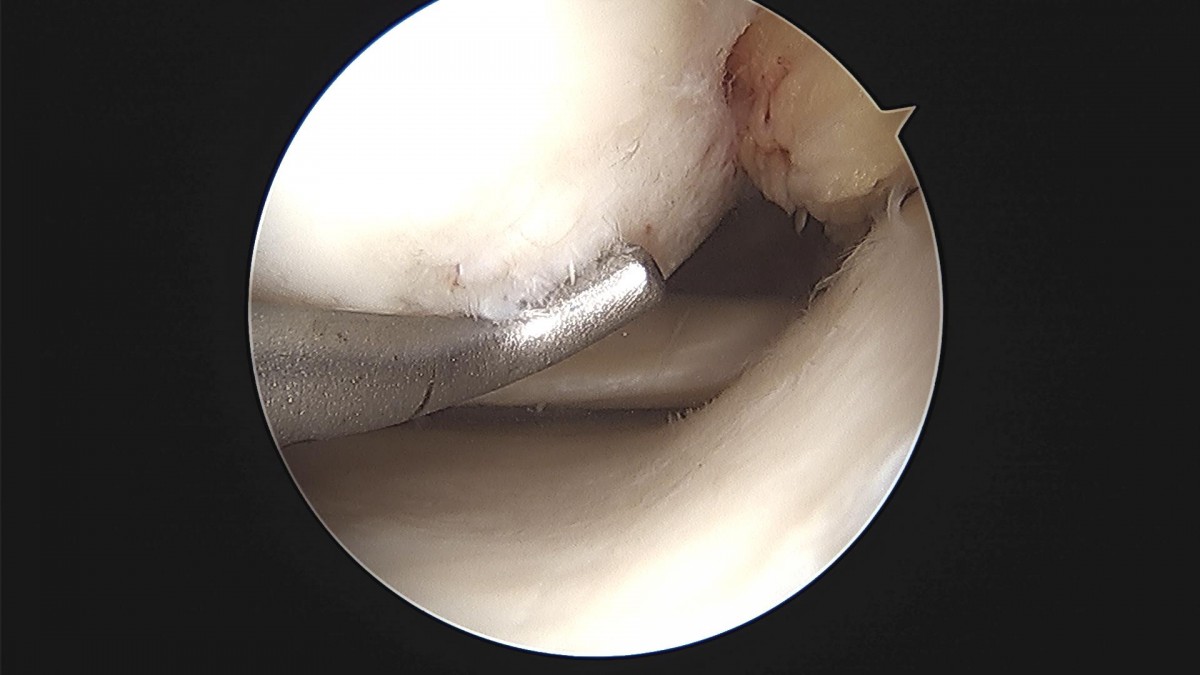

배우한 원장님 무릎 반월상 연골판 절제술 한복O 환자

8b0c7da4bf0a0c139df98fc62b3e688e_1702368995_9524.jpg